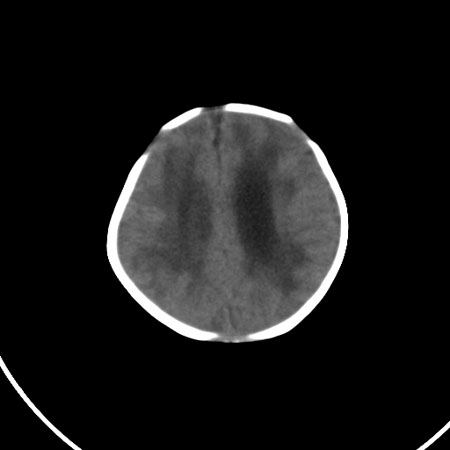

以下是引用小初学者在2009-1-10 17:51:00的发言:[br]考虑缺血缺氧性脑病后遗性改变。

以下是引用拾荒者在2009-1-10 19:23:00的发言:[br]生后有蛛网膜下腔出血病史,现幕上脑室明显扩张,脑室周围白质局限性密度减低,考虑hie脑病后遗表现。